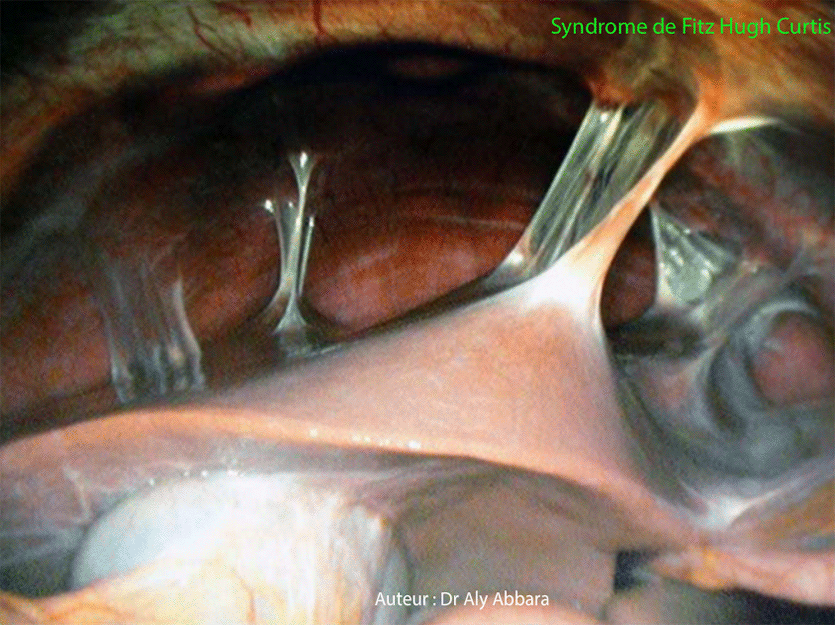

Image cœlioscopique montrant l'aspect typique d'une péri-hépatite (ou syndrome de Fitz Hugh Curtis). Ce syndrome se manifestant par la présence de nombreuses adhérences hépato-pariétales antérieures et hépato-diaphraqumatiques en cordes de violon. Chez cette patiente, l'exploration bactériologique montre qu'il s'agit d'une infection génitale haute avec pyosalpinx bilatéral ; le germe responsable et celui de chlamydia trachomatis. Consulter cette image montrant l'aspect cœlioscopique habituel est normal de la région péri-hépatique. |